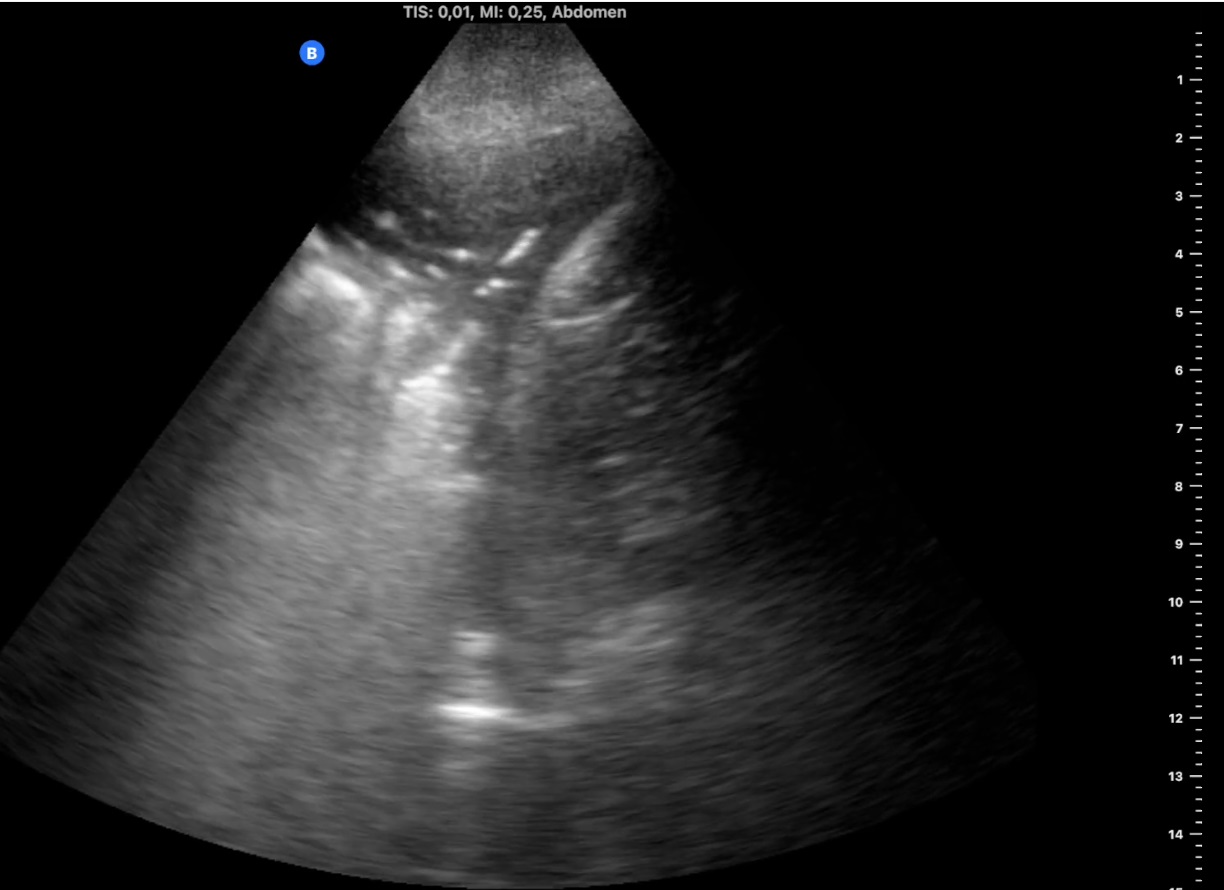

Varón de 95 años exfumador e hipertrofia benigna de próstata, en tratamiento con tamsulosina. Buena capacidad cognitiva con limitación de movilidad por edad y ausencia de ascensor. Aviso a domicilio por catarro de vías altas de 3 días, febrícula de 37,5 ºC desde el día anterior y dolor costal derecho con la tos y movimientos respiratorios. Tiene buen estado general, saturación 95% y en auscultación hipoventila en campo inferior derecho. Se realiza en domicilio ecografía pulmonar con ecógrafo portátil (imagen 1).

Hallazgos ecográficos

Consolidación con broncograma aéreo de 4 x 2 cm en campo posterolateral inferior derecho con leve derrame pleural adyacente al diafragma, y líneas B alrededor de la consolidación (imagen 2).